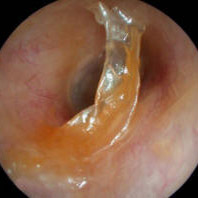

Ear tubes - The first picture shows an ear tube that has fallen out but is stuck to ear canal by ear wax. The last picture shows a T-tube, these stay in place much longer but run the risk of leaving a permanent perforation when finally removed.